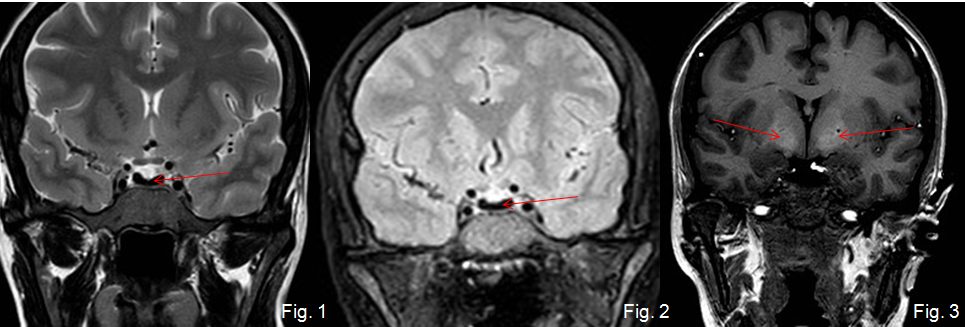

Mujer de 37 años con amenorrea que ingresa por poliuria y polidipsia. Antecedentes de anemia hemolítica no inmune, esplenectomizada. En tratamiento con metformina.

Depósito de hierro en la hipófisis secundario a hemocromatosis secundaria produciendo un hipogonadismo hipogonadotrófico.

La hemocromatosis secundaria es una enfermedad caracterizada por el depósito de hierro en el hígado y en otros órganos. El hierro se puede depositar en la hipófisis, ocasionando un hipogonadismo hipogonadotrofo.

En esta paciente se observa, además del depósito de hierro en la hipófisis, una hiperintensidad de señal de los ganglios basales, hallazgos que pueden ver en la degeneración hepatocerebral adquirida.

Tras la realización de esta RM hipofisaria se le realizaron a la paciente RM de abdomen y de corazón, existiendo también depósito de hierro hepático, pancreático y miocárdico, con diabetes mellitus secundaria.